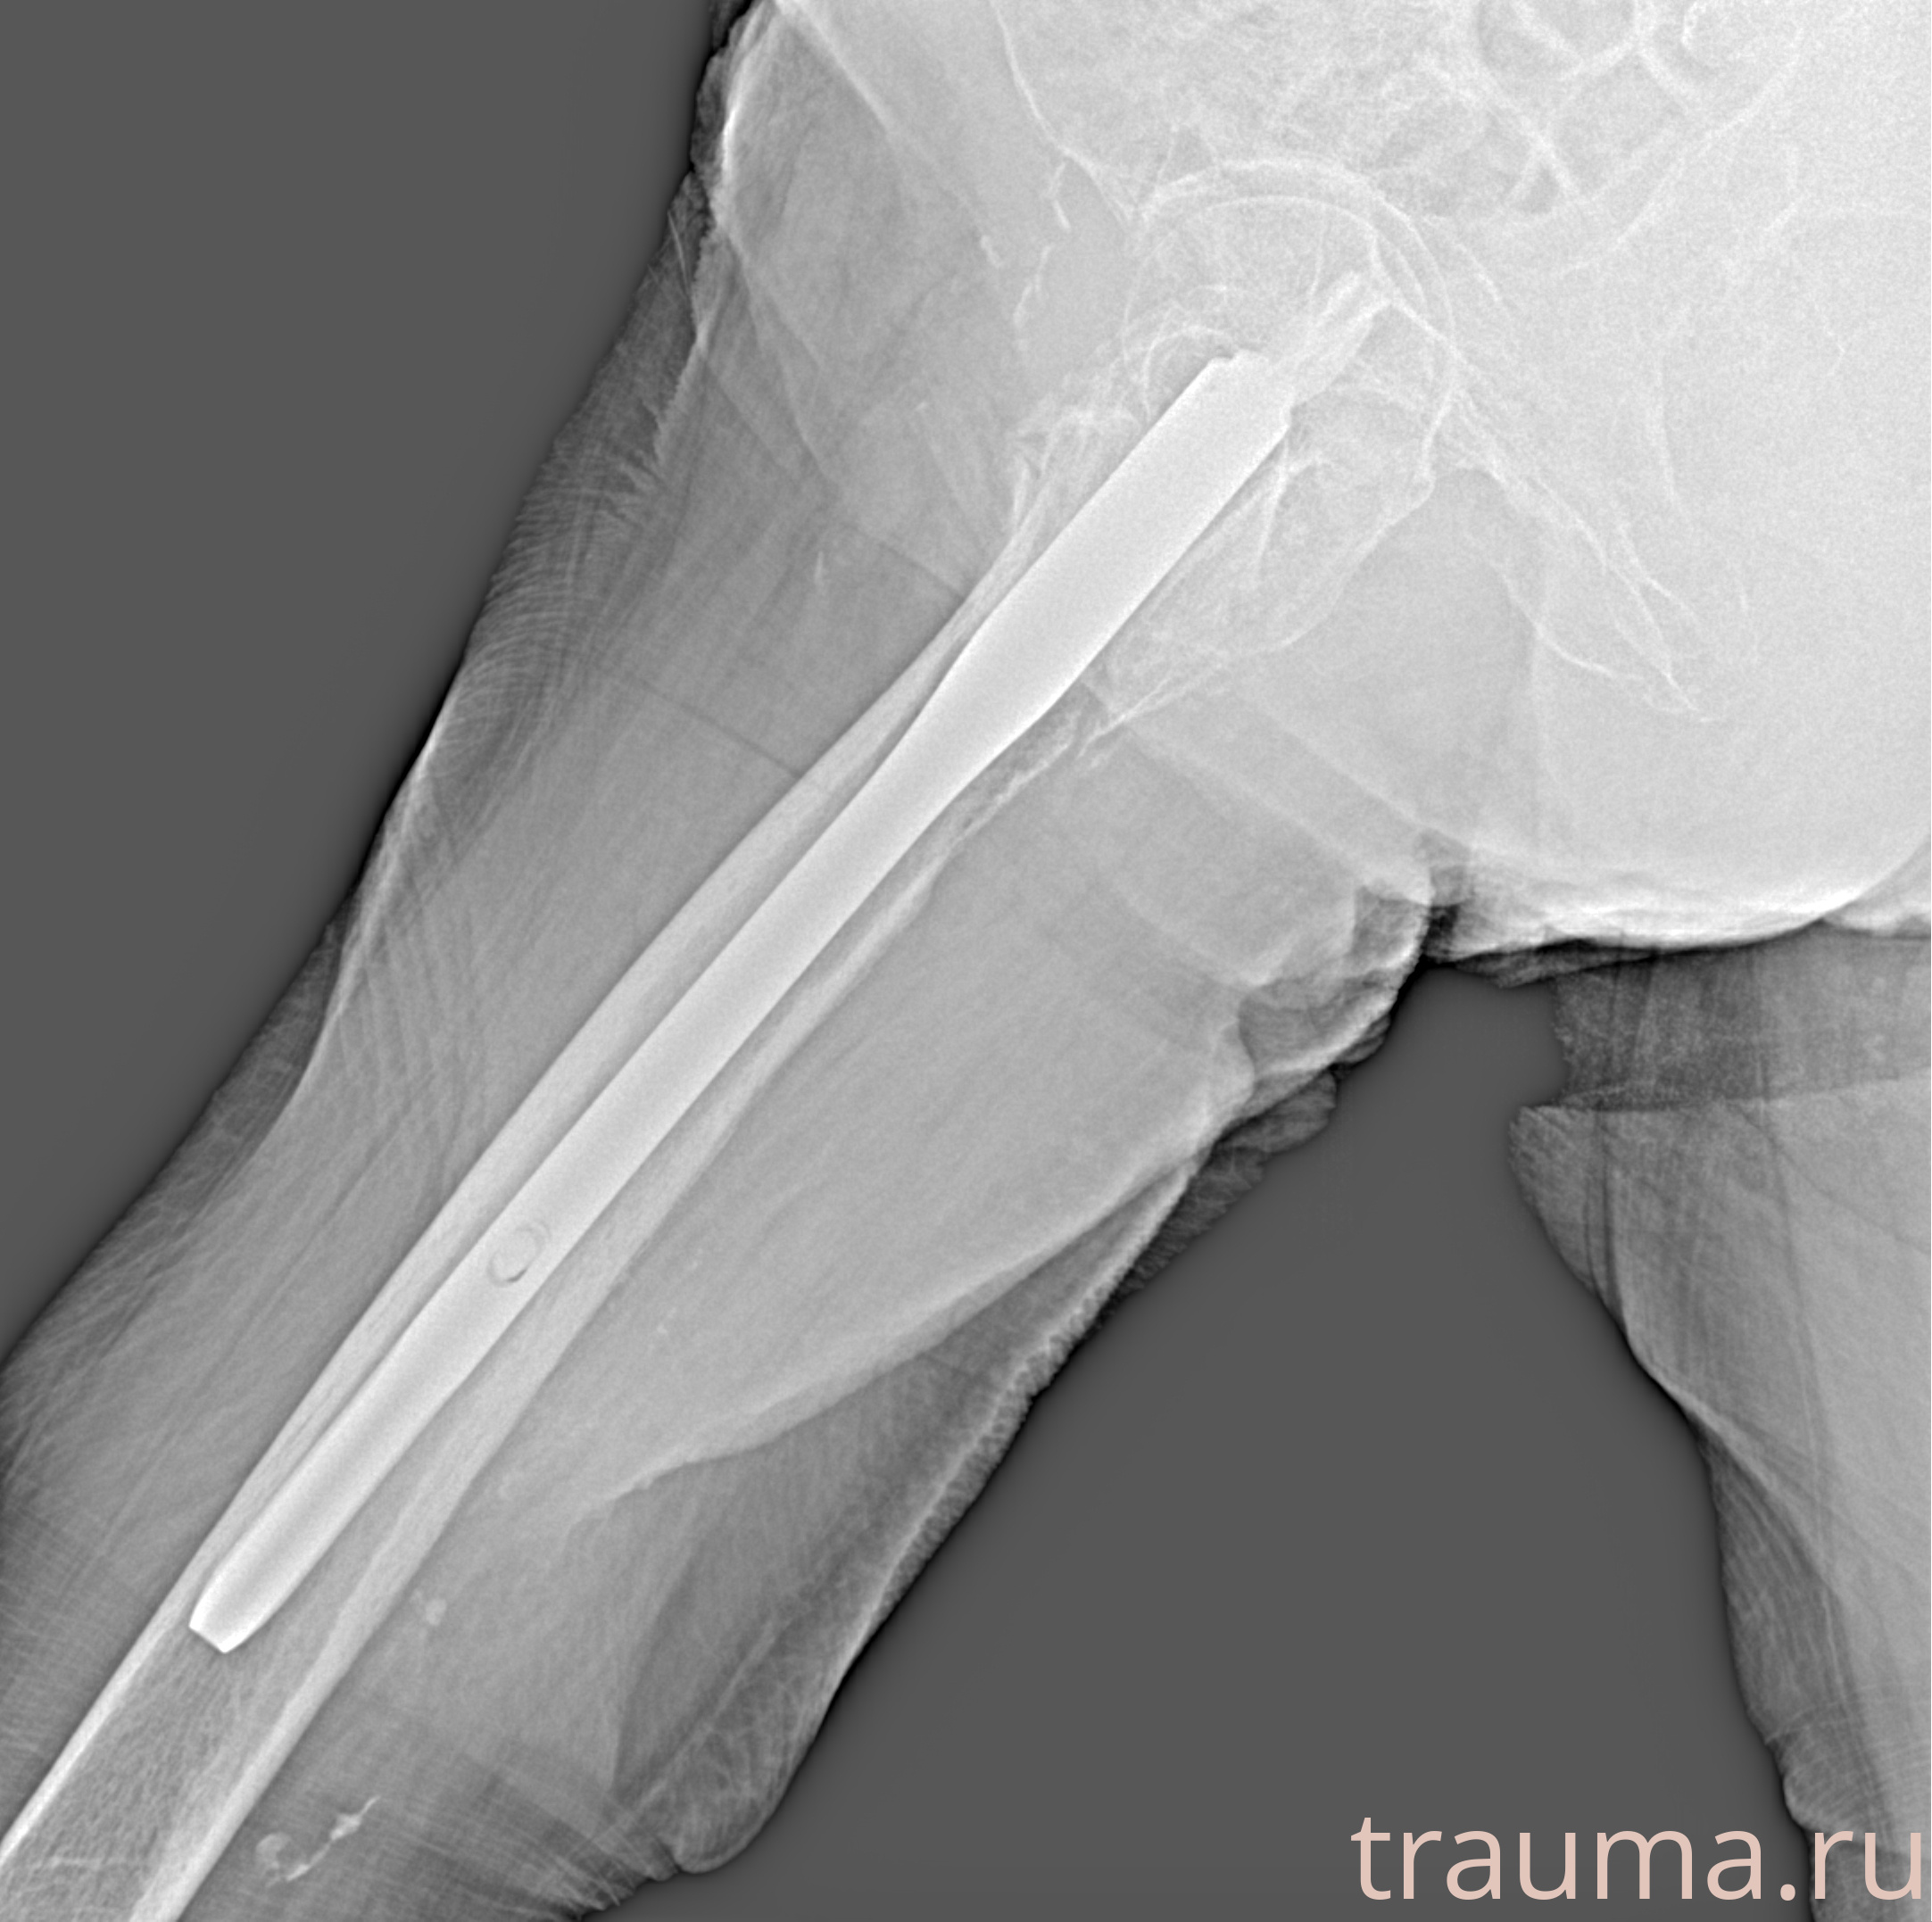

Рентгенограммы

Рентген на дому: по вашему адресу приезжает врач-рентгенолог, травматолог-ортопед с мобильным рентгеновским аппаратом, проводит диагностику травмы или заболевания, делает необходимые рентгенограммы, дает рекомендации по дальнейшему лечению. Получить качественные снимки в домашних условиях возможно благодаря уникальной методике, разработанной МосРентген Центром для института  Склифосовского